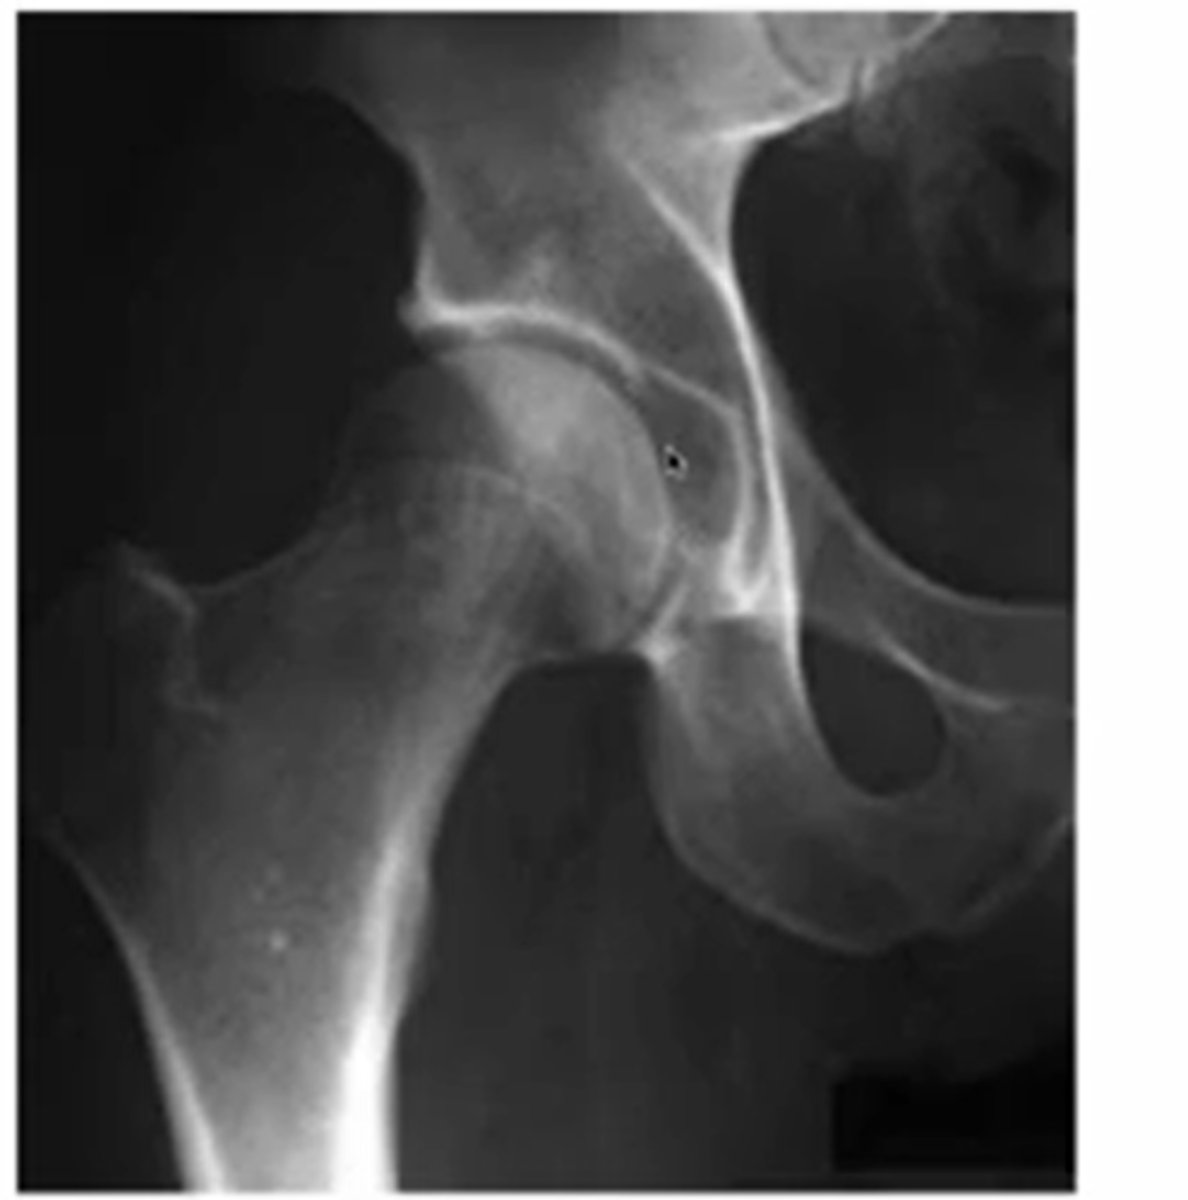

what does normal sclerosis at the hip look like and why

the whiter parts of the acetabulum

(because of WB)

what are the three indications for hip radiograph

hip pain

avascular necrosis

stress fractures